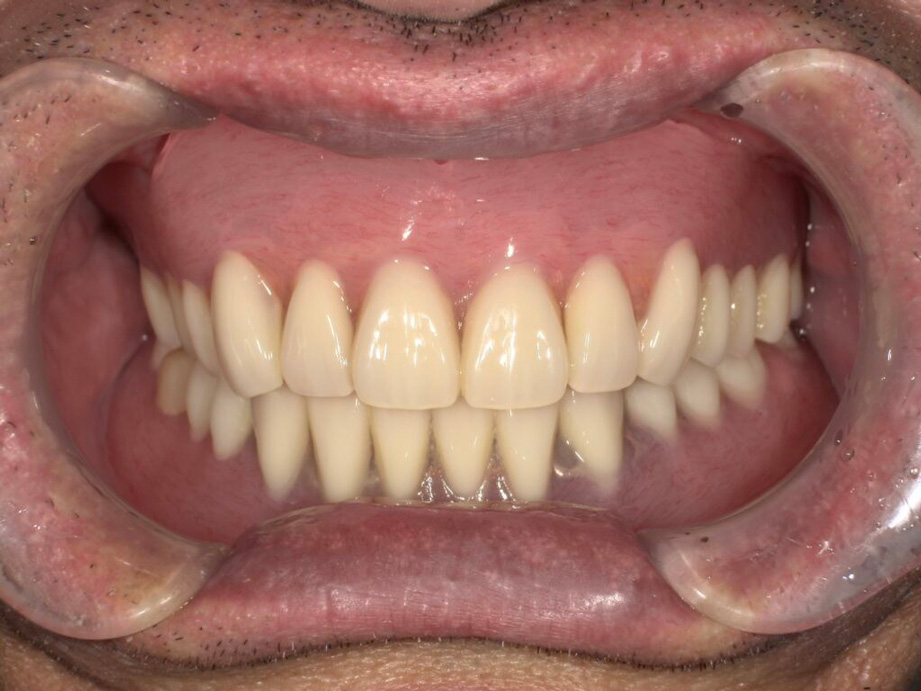

| 年代・性別 | 70代男性 |

|---|---|

| お悩み(主訴) | ずっと快適に食事をできるようにしたい。他の歯もなるべく失いたくない。 |

| 治療内容 | インプラント |

| 治療期間・回数 | 4ヶ月 |

| 費用 | 973,500円(税込) |

| リスク・副作用 | 治療後痛みが出るリスク、極めて稀に痺れが出るリスク |